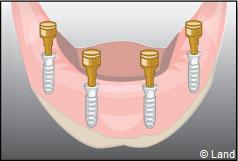

Les implants peuvent aussi servir à stabiliser un appareil amovible au maxillaire supérieur comme au maxillaire inférieur. Dans ce cas, les implants retiennent la prothèse amovible par des systèmes d’attachement.

Deux techniques sont possibles. Elles font appel à la barre de rétention ou aux boutons-pressions.